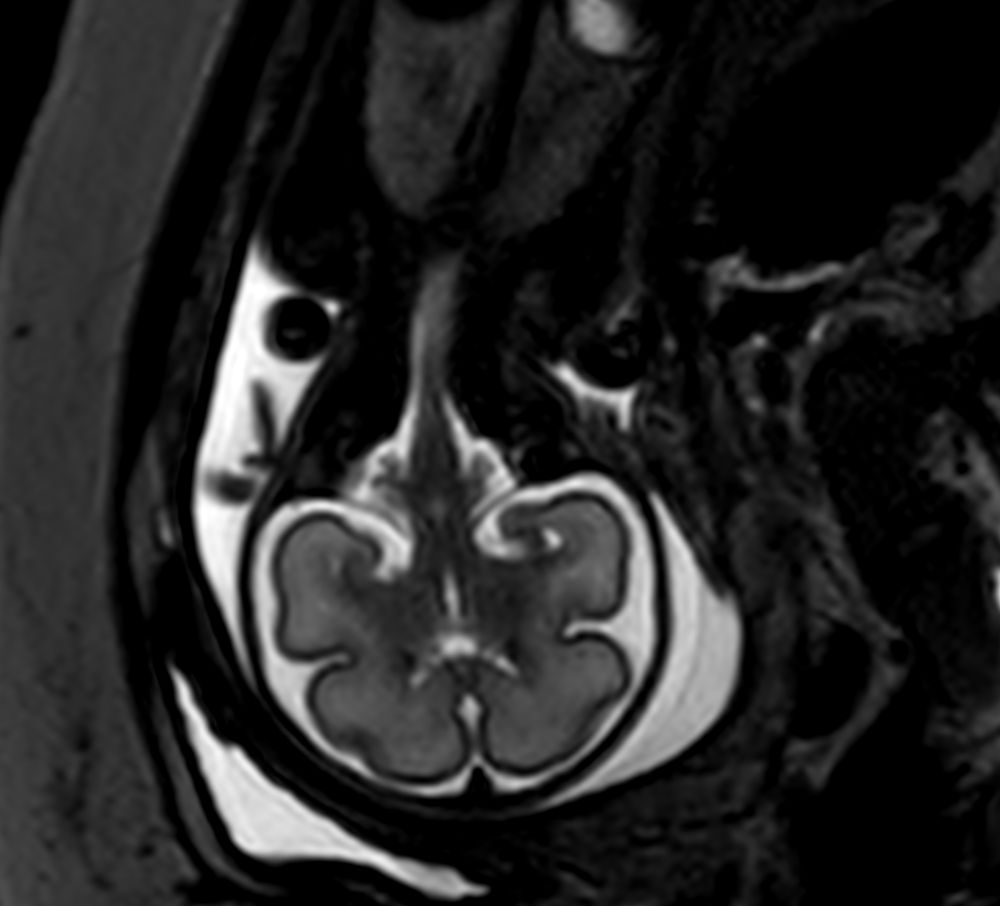

Coronal T2w TSE single shotCompressed SENSE